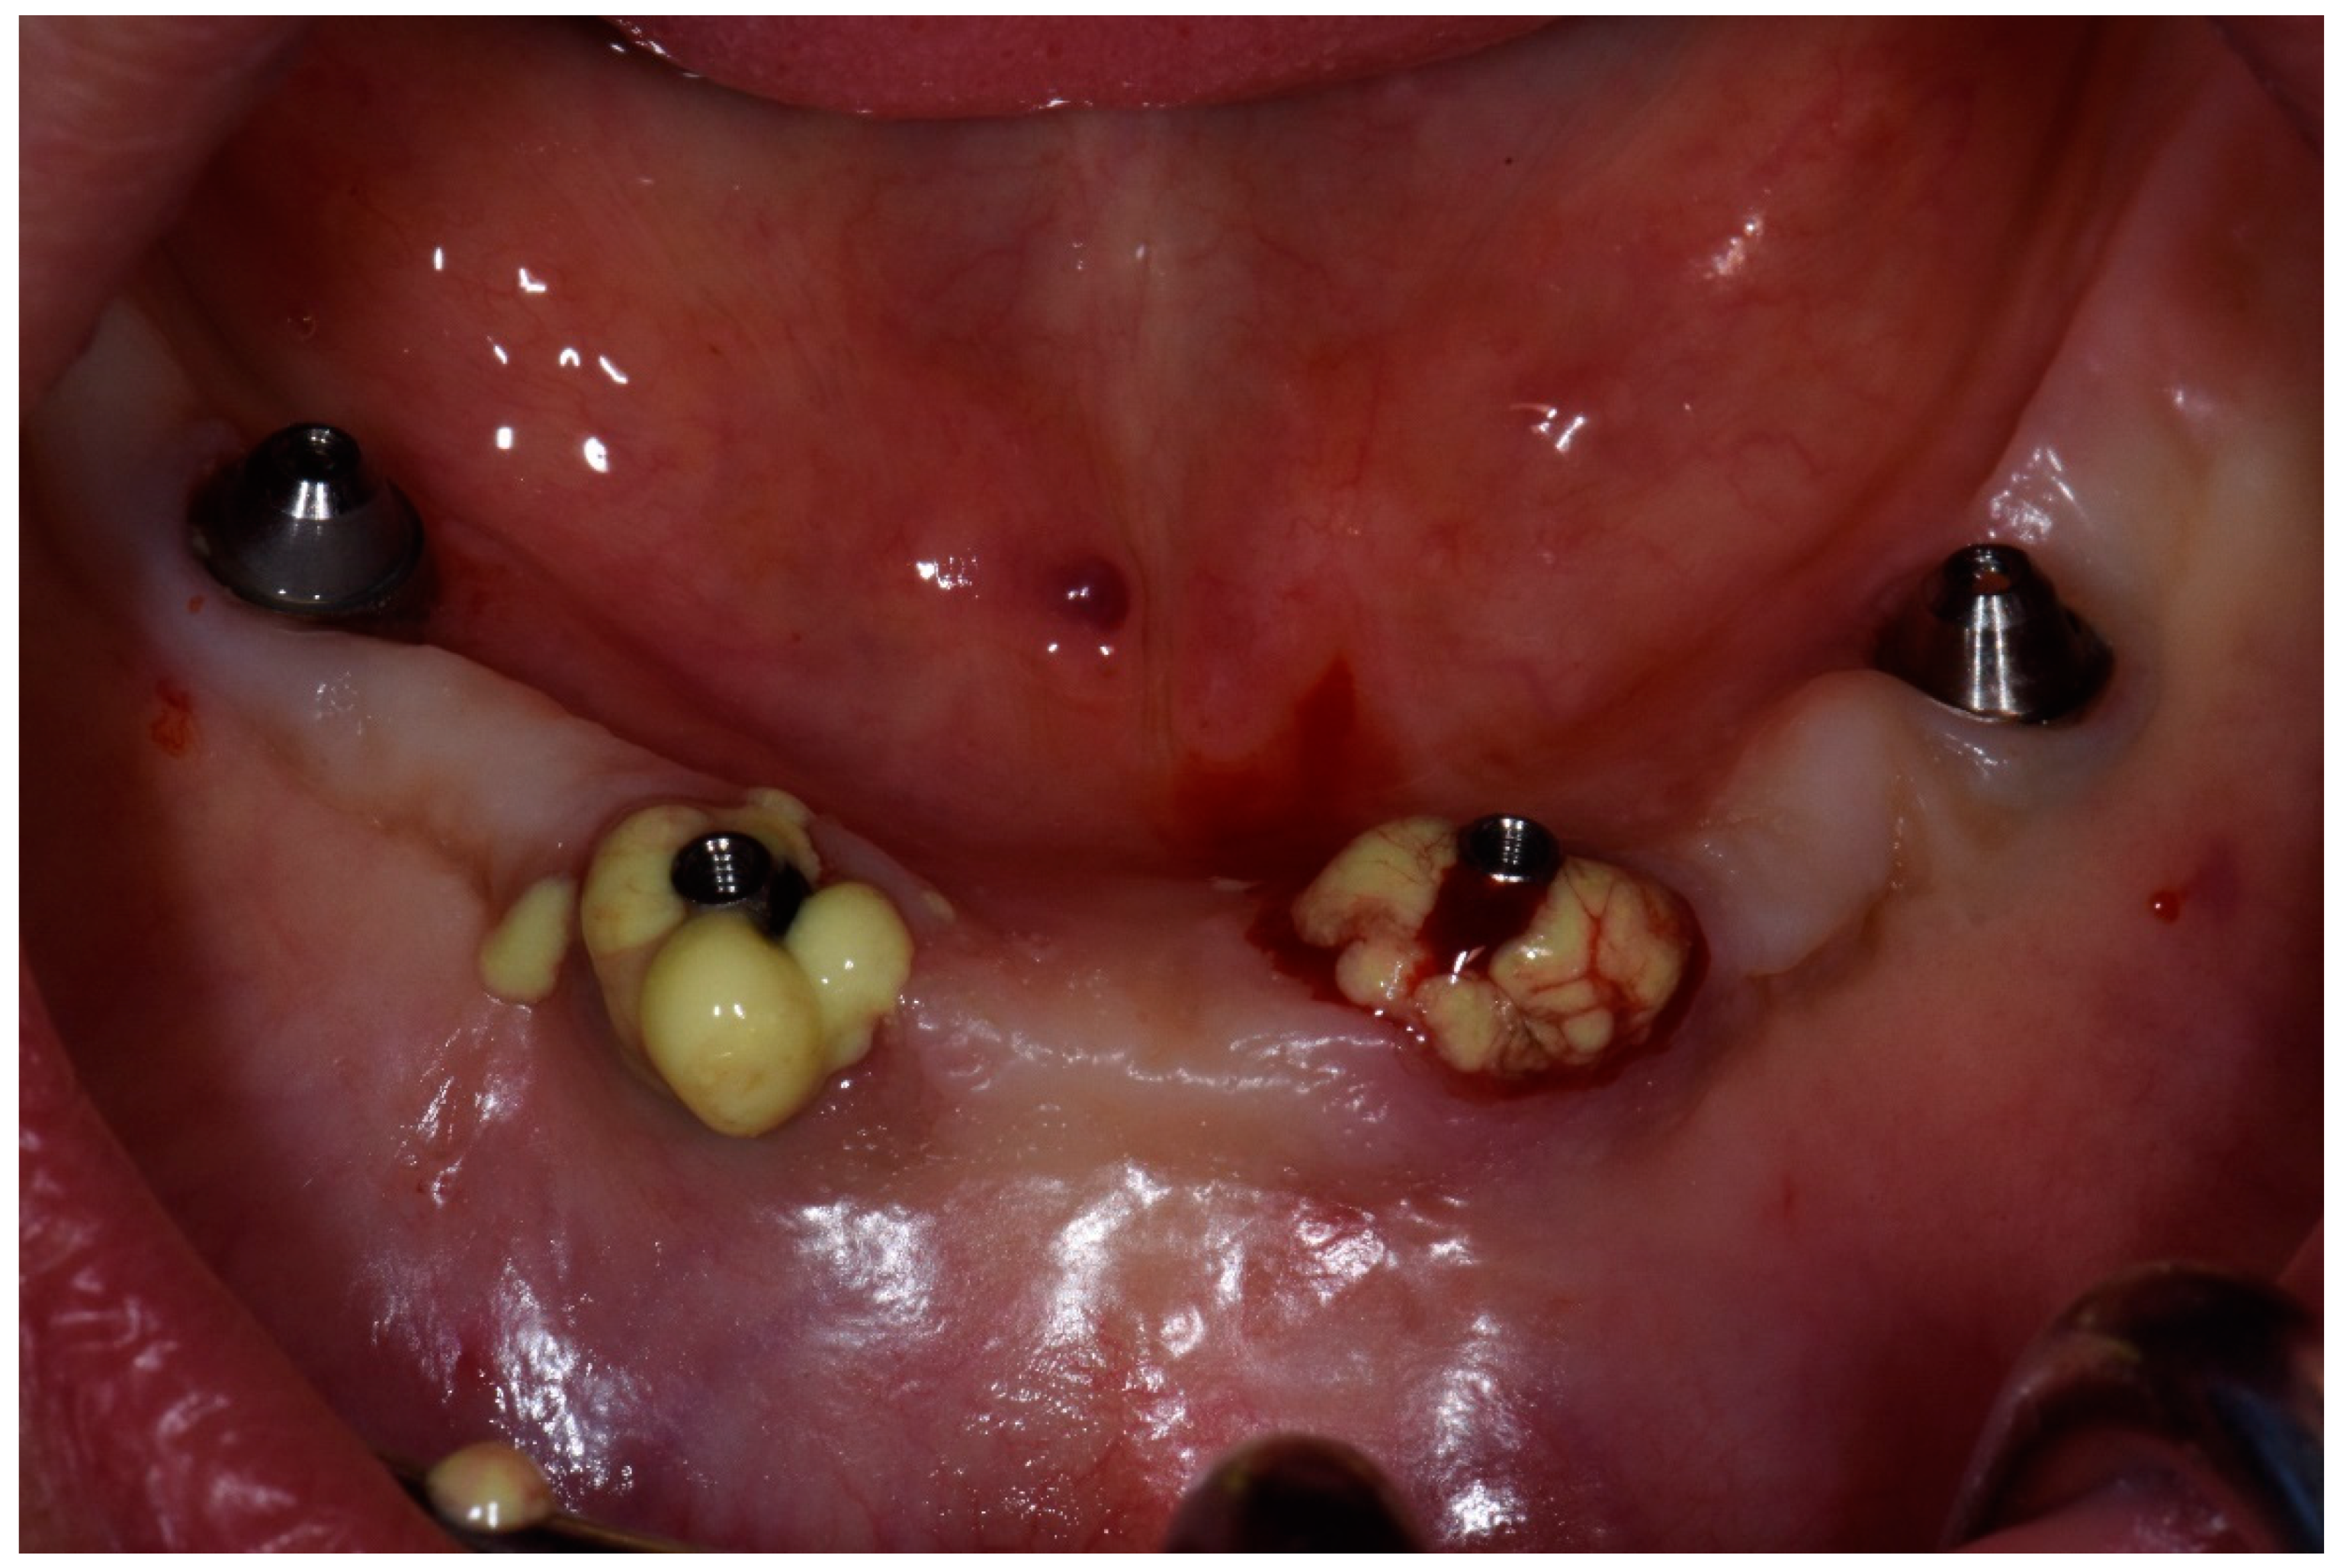

2.2. Case Report 2